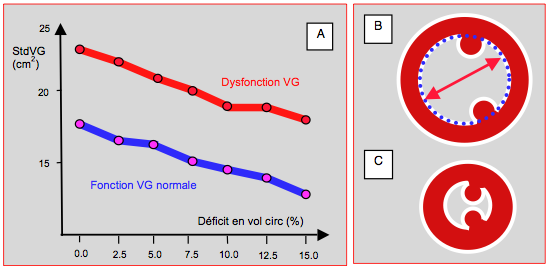

Mais si la cavité du VG se rétrécit au point que la paroi postéro-basale se déplace vers l’avant, le point de coaptation de la mitrale avance en direction de la chambre de chasse du VG (CCVG); l’occlusion n’a plus lieu sur le bord distal des feuillets mais entre l'extrémité du feuillet postérieur et le corps du feuillet antérieur. La partie distale de ce dernier flotte alors dans la cavité du VG, et l'élévation de la pression intraventriculaire la repousse antérieurement en direction de la CCVG. Par effet Venturi, elle est ensuite aspirée dans la CCVG, qu'elle occlut plus ou moins complètement. C’est le SAM (systolic anterior motion), qui survient en méso-systole (Figure 27.5) [4,17].

Figure 27.5 : Obstruction dynamique de la CCVG. A : situation normale. Le point de coaptation des feuillets mitraux est situé au tiers postérieur du diamètre antéro-postérieur (flèches bleues); en systole, la course radiaire de la paroi postéro-basale (*) est plus faible que celle de la paroi antéro-latérale; elle est activée électriquement en dernier. B: si le VG devient très petit par hypovolémie, la paroi postérieure avance en direction de la CCVG (flèche violette), parce que la zone antérieure est la jonction mitro-aortique qui est un point fixe (trigone fibreux); le point de coaptation est alors projeté vers la CCVG. En protosystole, la coaptation a lieu entre l'extrémité du feuillet postérieur et le corps du feuillet antérieur, dont la partie distale se retrouve flottant dans le VG et non en application contre le feuillet postérieur. C : en mésosystole, la pression intraventriculaire pousse le feuillet antérieur en direction de la CCVG (flèche violette) où l'éjection a commencé; celui-ci est alors aspiré par effet Venturi (flèche bleu pâle) et vient bloquer la CCVG (SAM: systolic anterior motion). Le débit aortique baisse soudainement, et la réouverture de la valve mitrale provoque une insuffisance méso-télésystolique (IM). MPP: muscle papillaire postérieur.

L’imagerie bidimensionnelle est le seul moyen de mettre en évidence un phénomène qui peut accompagner l’hypovolémie : l’obstruction dynamique de la chambre de chasse du VG ou effet CMO, par analogie avec la cardiomyopathie obstructive. Normalement, le point de coaptation de la valve mitrale est maintenu éloigné de la chambre de chasse par trois mécanismes: 1) il est situé au tiers postérieur du diamètre de la valve; 2) la paroi postérieure a moins de course radiaire que les parois antérieure et latérale; 3) la partie postéro-basale est activée électriquement en dernier (Vidéo). Lorsqu’elle s’élève en systole, la pression intraventriculaire maintient l’occlusion de la mitrale en appuyant les deux feuillets l’un contre l’autre par leurs bords distaux.

Mais si la cavité du VG se rétrécit au point que la paroi postéro-basale se déplace vers l’avant, le point de coaptation de la mitrale avance en direction de la chambre de chasse du VG (CCVG); l’occlusion n’a plus lieu sur le bord distal des feuillets mais entre l'extrémité du feuillet postérieur et le corps du feuillet antérieur. La partie distale de ce dernier flotte alors dans la cavité du VG, et l'élévation de la pression intraventriculaire la repousse antérieurement en direction de la CCVG. Par effet Venturi, elle est ensuite aspirée dans la CCVG, qu'elle occlut plus ou moins complètement. C’est le SAM (systolic anterior motion), qui survient en méso-systole (Figure 27.5) [4,17].

Figure 27.5 : Obstruction dynamique de la CCVG. A : situation normale. Le point de coaptation des feuillets mitraux est situé au tiers postérieur du diamètre antéro-postérieur (flèches bleues); en systole, la course radiaire de la paroi postéro-basale (*) est plus faible que celle de la paroi antéro-latérale; elle est activée électriquement en dernier. B: si le VG devient très petit par hypovolémie, la paroi postérieure avance en direction de la CCVG (flèche violette), parce que la zone antérieure est la jonction mitro-aortique qui est un point fixe (trigone fibreux); le point de coaptation est alors projeté vers la CCVG. En protosystole, la coaptation a lieu entre l'extrémité du feuillet postérieur et le corps du feuillet antérieur, dont la partie distale se retrouve flottant dans le VG et non en application contre le feuillet postérieur. C : en mésosystole, la pression intraventriculaire pousse le feuillet antérieur en direction de la CCVG (flèche violette) où l'éjection a commencé; celui-ci est alors aspiré par effet Venturi (flèche bleu pâle) et vient bloquer la CCVG (SAM: systolic anterior motion). Le débit aortique baisse soudainement, et la réouverture de la valve mitrale provoque une insuffisance méso-télésystolique (IM). MPP: muscle papillaire postérieur.